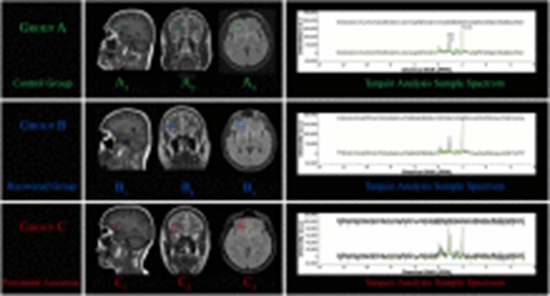

Background: While many COVID-19-induced anosmia patients recover their sense of smell within a few months, a substantial number of them continue to experience olfactory impairment. In our primary study, the metabolic patterns in orbitofrontal cortex (OFC) were observed to exhibit more alterations than other regions. Hence, this study specifically probes into alterations within OFC region in subjects with persistent COVID-19-induced anosmia.

Methods: In a new categorization, 54 subjects were studied as two major groups of COVID-19-related anosmia and normal each of which includes 27 subjects. Iran Recognition-Smell Identification Test (IR-SIT) over a three-month follow-up period was utilized for olfactory function assessment and anosmia diagnosis. Proton Magnetic Resonance Spectroscopy (1H-MRS) was employed to examine changes of metabolites in OFC, including N-acetyl aspartate (NAA), choline (Cho), and creatine (Cr), as well as their ratios. Additionally, a linear regression was applied to investigate the potential correlation between MRS data and IR-SIT scores.

Results: Patients with COVID-19-induced anosmia exhibited a significant reduction in NAA, Cho, and Cr levels in the OFC region compared to the control group. Moreover, NAA/Cho and NAA/Cr ratios were lower in the anosmia patients, whereas the Cho/Cr ratio elevated. The NAA/Cho ratio had the highest linear correlation with IR-SIT scores in anosmia.

Conclusion: This study highlights remarkable neurochemical patterns associated with COVID-19-induced anosmia in brain orbitofrontal cortex detectable by proton MRS, shedding light on the link between OFC function impairment and anosmia. The NAA/Cho ratio derived from MRS data emerged as a potential biomarker that correlates with anosmia severity and recovery examination.